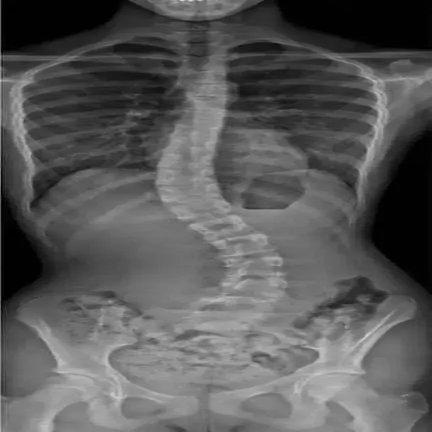

側弯症とは何か?

側弯症とは、背骨が左右に湾曲しながら回旋を伴う状態。